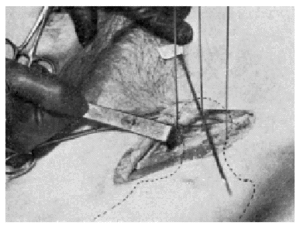

Con la finalidad de simplificar la técnica y ahorrar exámenes radiográficos hemos intentado precisar exactamente la situación topográfica del centro de la cabeza femoral. En 9 cadáveres, en ambos lados, con las articulaciones coxofemorales colocadas en el mismo grado de abducción y rotación interna que en el acto operatorio (distancia entre los talones, de 65 a 70 cm., y rotación interna del pie, de 30 a 40°), hemos hallado que el centro de la cabeza femoral correspondía a la piel de la región inguinocrural a un punto preciso: el lugar de entrecruzamiento de una línea horizontal que pase inmediatamente por el borde superior del pubis con otra línea que siga el trayecto de la arteria femoral por su parte externa (figs. 9, 10, 11 y 12). En dicho punto clavamos verticalmente, hasta que se insinúe en el hueso, una aguja de Kirschner, provista de un mango adecuado que permita hacer presión. La introducción de la aguja mediante un taladro tiene un peligro: el que se enrollen alrededor de aquellas ramas del nervio crural, como hemos podido comprobar nosotros en el cadáver.

Figura 9. Experiencia cadavérica núm. 2. Se ha clavado verticalmente un Kirschner en el lugar de entrecruzamiento de una línea horizontal que pasa inmediatamente por el borde superior del cuerpo del pubis, con el borde externo de la arteria femoral.

Figura 10. Experiencia cadavérica núm. 2. El mismo caso de la figura anterior. Se han colocado dos Kirschner verticales: uno, inmediatamente por encima, y otro, inmediatamente por debajo de la periferia del borde posterior de estos dos tercios de esfera que representa la cabeza femoral.

Como punto de entrada del alambre conductor a nivel de la región trocantérea buscamos la intersección de una línea que descienda siguiendo la dirección del fémur, a partir del punto más prominente del trocánter, con otra línea perpendicular a aquélla, que pasa por el tubérculo innominado y que sirve de inserción al vasto externo (fig. 13).

Figura 13. Obsérvese cómo de la intersección de una línea que desciende siguiendo la dirección del fémur a partir del punto más prominente del trocánter, con otra línea perpendicular a aquella que pase por el tubérculo innominado, A, que sirve de inserción al vasto externo, resulta un punto ideal para entrada del clavo.

Al aplicar dicha técnica en el vivo, hay que tener sumo cuidado de que la línea que pasa por ambas espinas ilíacas anterosuperiores se mantenga perpendicular a la línea xifoidea púbica (véase la fig. 14).

Figura 14. A: radiografía obtenida sin exploración radioscópica previa. Obsérvese cómo el alambre de Kirschner que pasa inmediatamente por encima de la espina del pubis, corresponde, en ambos lados, exactamente a la fosita de inserción del ligamento redondo. El fémur, en ambos lados, está colocado en la misma posición que en el acto operatorio. B: si se bascula la pelvis, y por lo tanto, la línea que pasa por ambas espinas ilíacas anterosuperiores deja de ser perpendicular a la línea xifoidopúbica, deja de tener valor el punto de referencia que preconizamos.